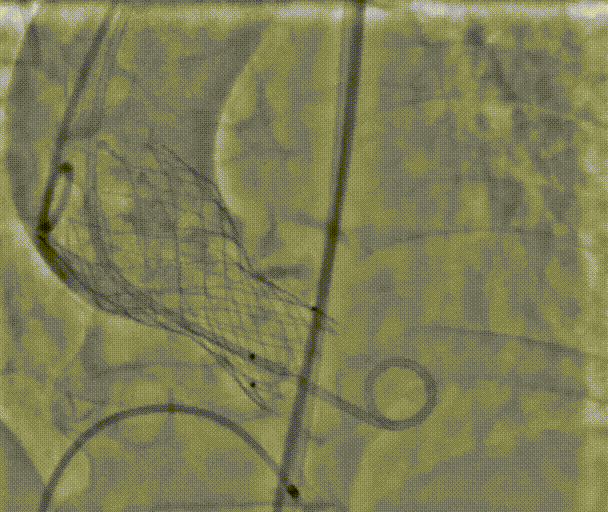

术中操作

植入的主动脉瓣膜